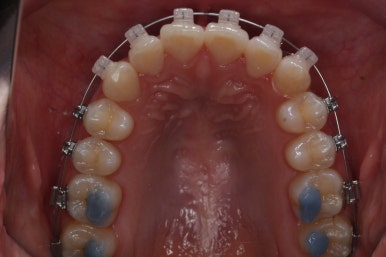

부산부정교합 키다리아저씨치과에서 장치를 처음 부착한 모습입니다.

많이 삐뚤어진 부위는 철사가 굽이굽이 지나가는 것을 볼 수 있습니다. 이 철사가 점점 직선으로 가지런해지면서 치아가 바르게 가지런해집니다.

부산부정교합 키다리아저씨치과에서 처음 장치를 부착한 모습입니다.

지그재그 방향으로 치열이 변해가는 중입니다.

이렇게 덧니가 가지런해지는데 1년도 채 안걸렸습니다.

마찬가지로 지그재그 방향으로 치열이 변해가는 모습입니다.

윗니들만 보면 이런 모습으로 변해가고 있습니다.